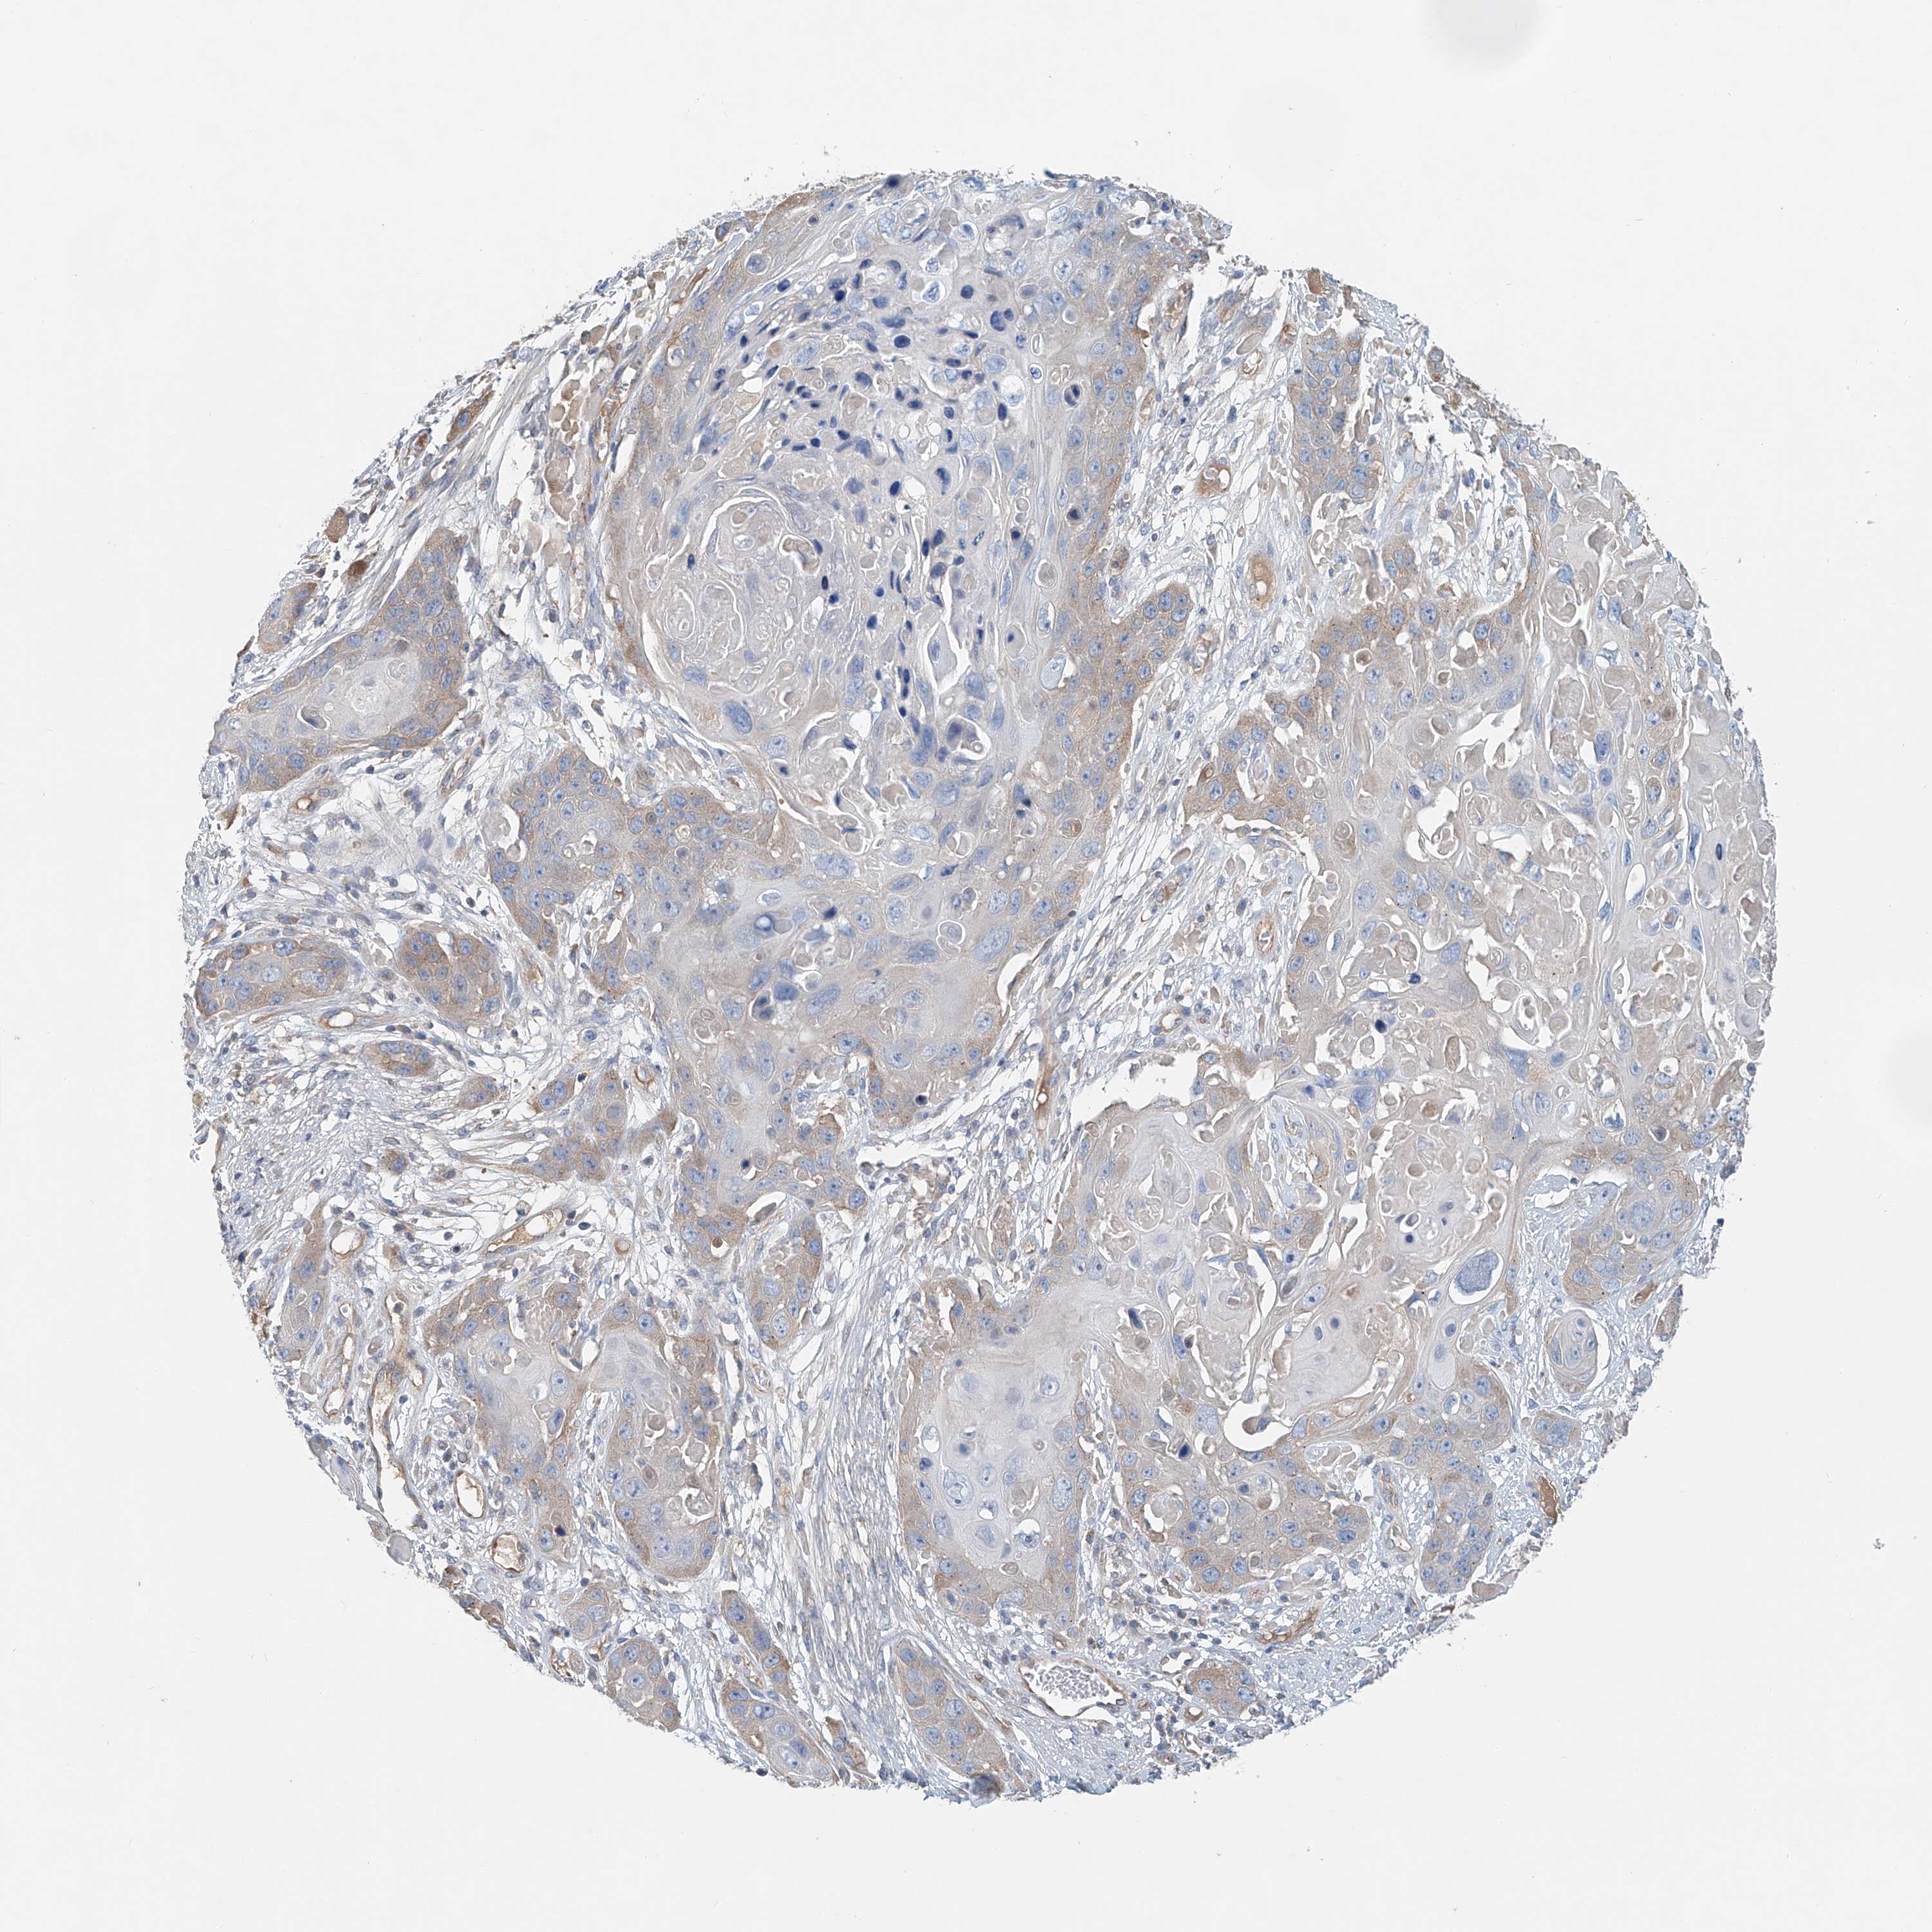

CANCER SKIN CANCER Show tissue menu

Basal cell and squamous cell cancer

SKIN CANCER - Protein expressioni

A mouse-over function shows sample information and annotation data. Click on an image to view it in a full screen mode. Samples can be filtered based on level of antibody staining by selecting one or several of the following categories: high, medium, low and not detected. The assay and annotation is described here.

Each image is clickable and will lead to virtual microscopy that enables deeper exploration of all samples and also displays staining intensity scores, fraction scores and subcellular localization as well as patient and tissue information for each sample.

Antibody HPA031106

Basal cell carcinoma

Squamous cell carcinoma, NOS

Squamous cell carcinoma, metastatic, NOS